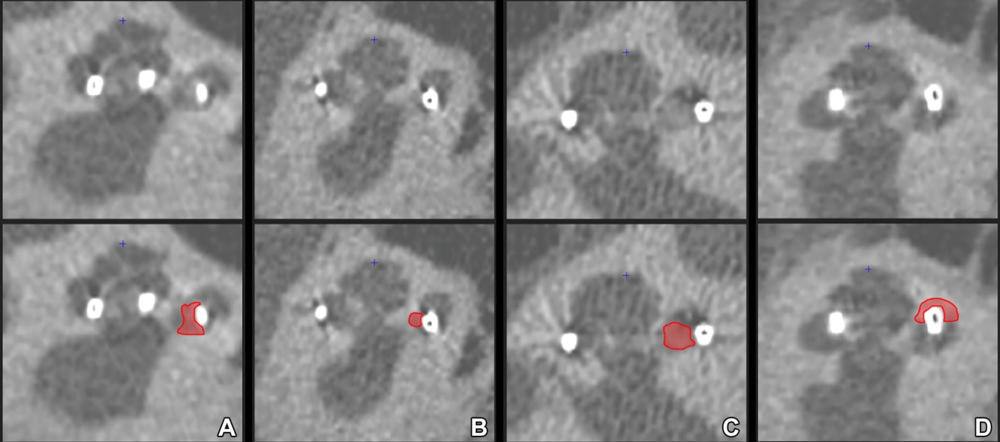

Figure 4. Midmodiolar ultra-high-spatial-resolution CT scans with corresponding annotations indicating new bone formation (NBF) in red. Note the varying appearance of NBF, ranging from (A) slightly increased attenuation, resembling that of the modiolus, to (D) frank ossification with an attenuation similar to that of the otic capsule surrounding a translocated contact in the scala vestibuli. An intermediate form of NBF appearance is shown in B and C. Moreover, in B, the ossification between the perimodiolar positioned electrode contact and the medial cochlear wall is difficult to discern, resulting in interrater disagreement.